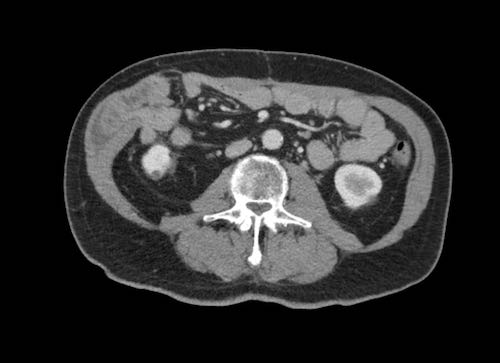

Ca lâm sàng 2

Cuộn qua các lát cắt.

Bạn có thể phát hiện tất cả các tổn thương cấy ghép phúc mạc không?

.jpeg)